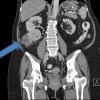

Cancer treatment options such as chemotherapy, radiotherapy, nano-medicine, and surgery are among the many techniques available to cancer patients. However, the large volume of research in this field has given birth to a new range of issues, such as choosing the appropriate implementation, and the often high cost of such treatments. Among the many treatments routinely prescribed to cancer patients are anti-angiogenic drugs such as tyrosine kinase inhibitors (TKIs). Such drugs are extremely expensive, and may cause numerous side-effects in the patient. Therefore, a reliable anti-angiogenic predictor which can help determine the projected outcomes of such treatments may be highly useful. Researchers from the Institute of Bioengineering and Nanotechnology (IBN), Singapore General Hospital (SGH), and National Cancer Centre Singapore (NCCS) have developed a test kit which they believe will help to address these concerns, in patients diagnosed with clear cell renal cell carcinoma (ccRCC), one of the three major types of kidney cancer.

According to the study in European Eurology, the researchers have developed a practical, eight-gene assay which is able to determine the particular subtype of the measured ccRCC sample. The researchers performed a whole-genome expression analysis on samples with material from 55 ccRCC patients, and compiled the results into different categories, with different probable responses to treatment. The assay may be used to distinguish patients into groups with different survival and treatment outcomes, by comparing their particular ccRCC profile to the research conducted in the study. Patients suffering from renal cell carcinoma may benefit from this technology, as it may determine the potential for a successful anti-angiogenic TKI implementation, as well as the survival potential of the patient. In light of the high price of TKIs, and the threat of potential side-effects, the test kit could prove to be a highly beneficial piece of technology.